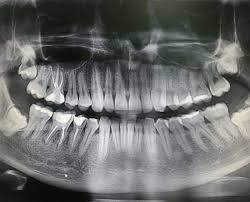

Панорамний знімок загальний (P1)

Ортопантомограма (ОПТГ) потрібен щоб:

• Оцінити стан зубів, коріння, каналів. А також побачити пломби, імпланти, коронки, проаналізувати структуру тканин пародонту.

• Виявити приховані запальні процеси, каріозні порожнини, патологічні утворення (кісту, абсцес).

• Виявити пародонтальні кишені.

• Провести оцінку стану навколозубних тканин, верхньощелепних синусів, скронево-щелепного суглоба.

• Визначити параметри щелепної кістки, положення, стан зубів у ряду, включаючи зуби мудрості.

• Хоча панорамний знімок — один з основних діагностичних інструментів стоматолога, він має деякі похибки:

• Геометричні спотворення, що не дають 100% точність зображення (корекція змін становить 20%).

• Навіть мінімальне зміщення щелепи обумовлює зміщення фокусної плями, через що зображення стає стисненим або розтягнутим.

• Через структурні відмінності у тканинах, що потрапили в зону дії рентгенівського випромінювання, щільні тканини не дають достовірно оцінити стан менш щільної губчастої кістки.

• Двовимірний знімок щелепи зубів не оцінює форму кісткового гребеня, структуру кістки на рівні, що цікавиться.

Ортопантомограма — це швидше допоміжний діагностичний інструмент, що надає оглядову картину і виявляє явну патологію. На відміну від панорамного знімка, 3D комп’ютерна томографія дає не одне плоске зображення щелепи. Лікар отримує низку послідовних зображень у різній проекції без спотворень, властивих панорамного знімка. Отримане тривимірне зображення дозволяє лікарю розглянути щелепно-лицьову зону на будь-якій глибині з усіх боків та кутів. Приклад: на панорамному знімку видно правильний імплант, а на КТ дослідженні виявлені помилки при встановленні.